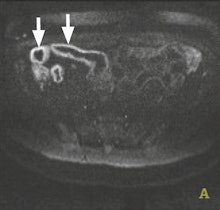

The application of DWI is well-established in helping to detect and characterize disease in the brain and liver, but it is relatively new in Crohn's disease. Key to management of this chronic relapsing disease of the bowel is differentiating between active inflammatory disease and chronic fibrosis because this helps determine whether the patient will be treated with immunosuppressive drugs or surgical resection.

Dr. Stuart Taylor from London.Gastrointestinal imaging specialists believe there is compelling evidence that bowel affected by Crohn's disease leads to abnormal DWI,and there is considerable interest in whether DWI can help aid both detection of affected bowel and differentiation of active disease from fibrosis, according to Dr. Stuart Taylor, consultant gastrointestinal radiologist and professor of medical imaging at University College London. He is concerned about how the inflammatory process affects the movement of water, yielding abnormal DWI signal.

"In theory the greater the inflammation, the more abnormal the DWI signal," he said in an interview ahead of the congress.

However, recent information correlating MRI with histopathological examination of surgical resection specimens suggests chronic fibrosis could affect DWI signal in a similar way as inflammation. This means that when there is a question about fibrosis, for example in longstanding disease or in patients who are still symptomatic after long drug treatments, DWI probably should not be used on its own for differentiation. Instead, the radiologist should deploy conventional T2 and contrast-enhanced sequences which can help differentiate active versus nonactive disease.

"In the literature, one suggested role for DWI is to replace enhanced sequences. However, we need further evidence that such replacement will not impact on the ability of the radiologist to distinguish whether there is predominantly inflammation (active disease) or fibrosis (nonactive disease)," said Taylor, stressing that such differentiation was fundamental to determining treatment pathways.

He envisages that high sensitivity of DWI for abnormal bowel will give it a role in initial staging of the small bowel in newly diagnosed patients. It will also be useful in established Crohn's disease cases for defining how active the disease is, and particularly for monitoring therapy response during treatment. Taylor reports particular use of DWI by pediatric radiologists as a sensitive, minimally invasive method to identify abnormal bowel in young children. In addition, DWI may replace sequences using intravenous contrast, particularly if detection of fibrosis is not the main clinical question.

"The question that now needs to be addressed is whether or not DWI should be a part of routine practice every time there is a suspicion of Crohn's disease, or if it should be reserved for selected cases, for example to monitor activity change during or after treatment, or in a newly diagnosed patient to establish the exact location of the disease," he noted.